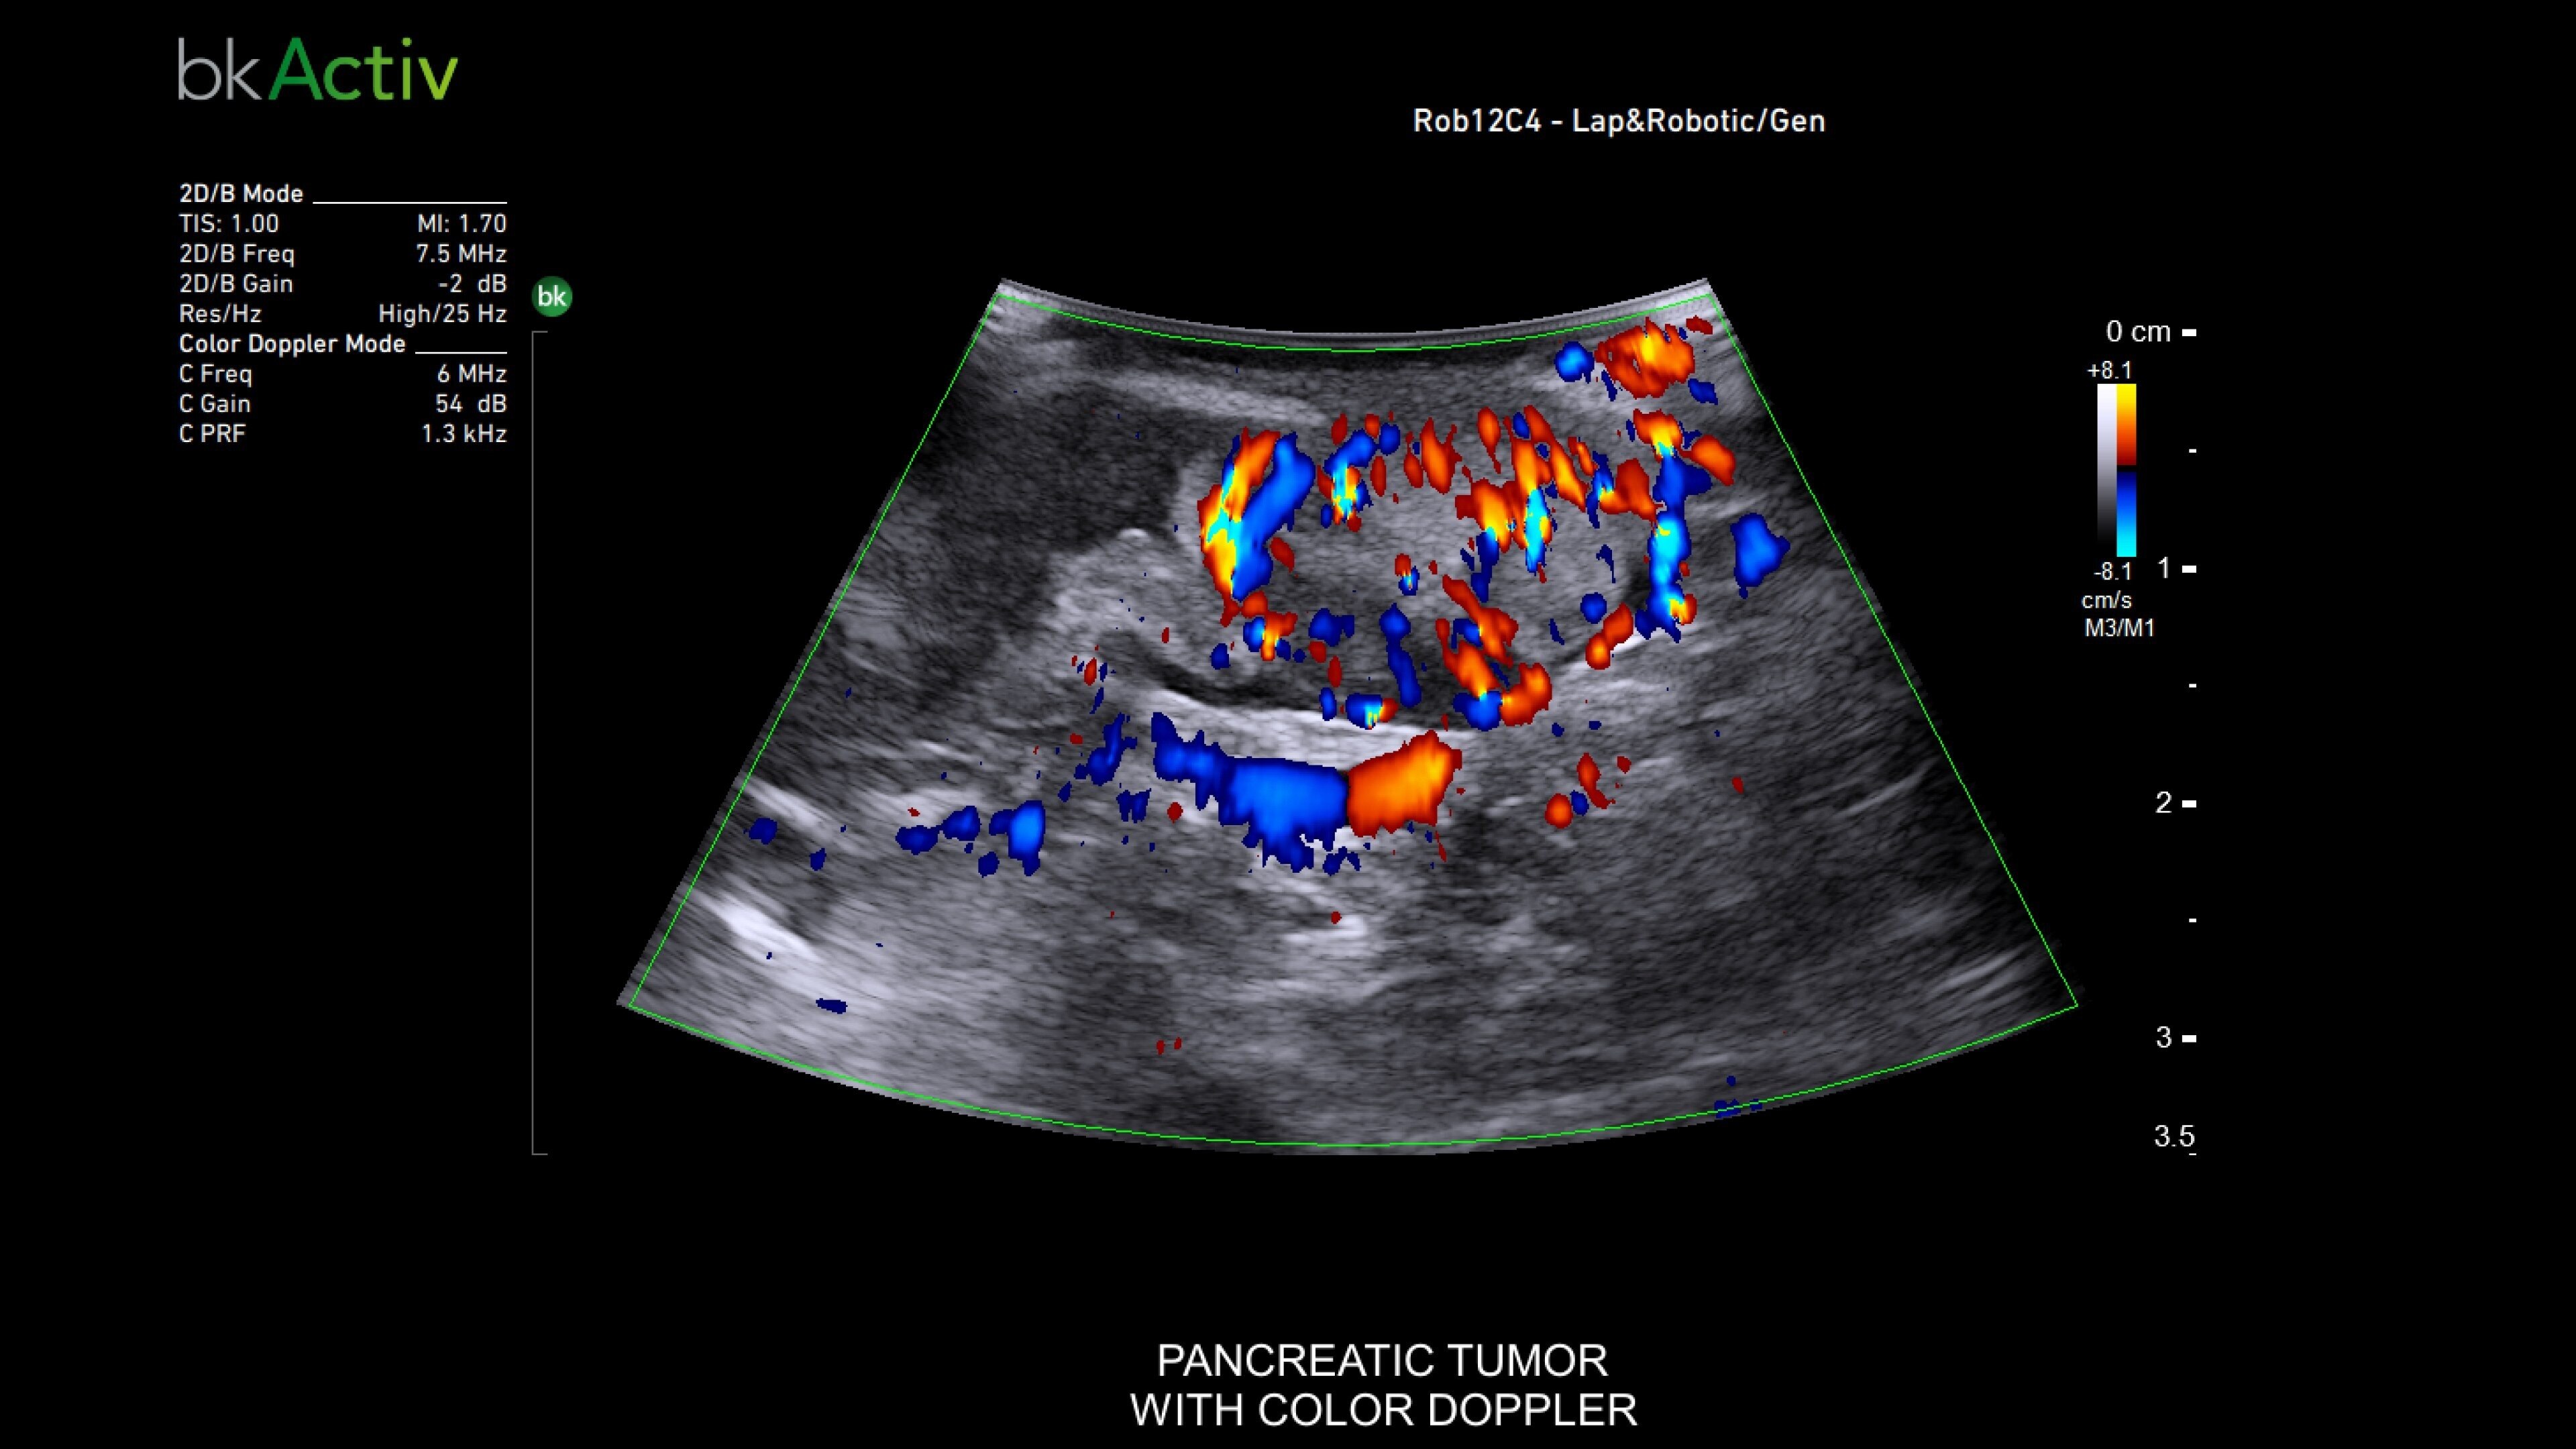

The bkActiv is a high-performance imaging system offering detailed, real-time surgical visualization. Refined through extensive research and user feedback, it supports remarkable imaging of areas of interest–neurosurgical (neuro-oncology, spine, neurovascular), urology (prostate, kidney, and bladder), hepatobiliary, colorectal, and pelvic floor.

It features technology such as Dual Live Compare for live image comparion, stored image compare, mirror image to see a live iUS image on the touch screen and sensitive color Doppler visualizes blood flow during complex surgeries.

General surgery

Enhanced visualization for general surgery

The bkActiv ultrasound system delivers remarkable imaging for general surgery, including anorectal, robotics-assisted, and pelvic floor surgeries. Its advanced algorithms provide uniform image resolution and greater detail, while the remote control allows surgeons to adjust images within the sterile field. For anorectal surgeries, bkActiv offers high-definition imaging to visualize normal and abnormal anatomy, including anal sphincter injuries and rectal cancer. In robotics-assisted surgeries, the system's robotic transducers provide real-time, high-resolution imaging to locate and assess lesions and critical structures. For pelvic floor surgeries, bkActiv's advanced 3D architecture supports dynamic, real-time examination during procedures.